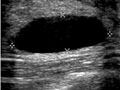

Una ecografía de seno usa ondas sonoras para formar una imagen de los tejidos que se encuentran dentro del seno. Una ecografía de seno puede mostrar todas las zonas del seno, incluida la zona más cercana a la pared torácica, que es difícil de evaluar con una mamografía. La ecografía de seno no usa rayos X ni otros tipos de radiación posiblemente perjudiciales.

Una ecografía de seno se usa para ver si un bulto en el seno está lleno de líquido (un quiste) o si es un bulto sólido. Una ecografía no reemplaza la necesidad de una mamografía, pero con frecuencia se usa para revisar resultados anormales de una mamografía.

En una ecografía de seno, una unidad pequeña manual, que se llama transductor, se desliza suavemente de un lado a otro del seno. Una computadora convierte las ondas sonoras en una imagen, en una pantalla de televisión. La imagen se llama sonograma o ecografía.